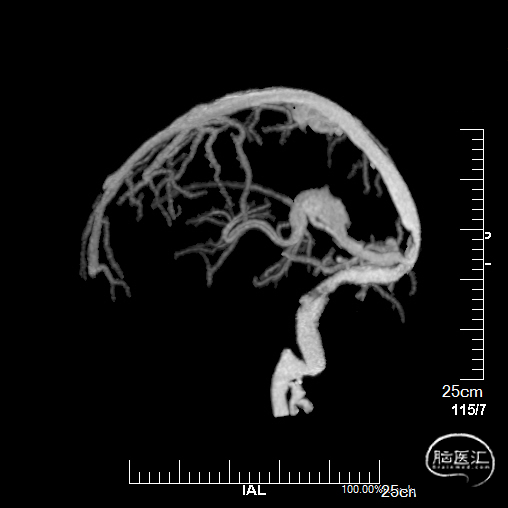

术前CTV:左侧颈内静脉、乙状窦、横窦闭塞,血栓形成。

术前MRV提示血栓负荷不断增加。

术前复查MRV提示血栓累及范围继续扩大。

经中间管手推造影,确认血栓位置。

球囊扩张和接触溶栓后,再次经中间管反复抽吸后复查造影。

再次给予尿激酶10万U后复查造影。

再次给予球囊扩张,球扩后复查造影。